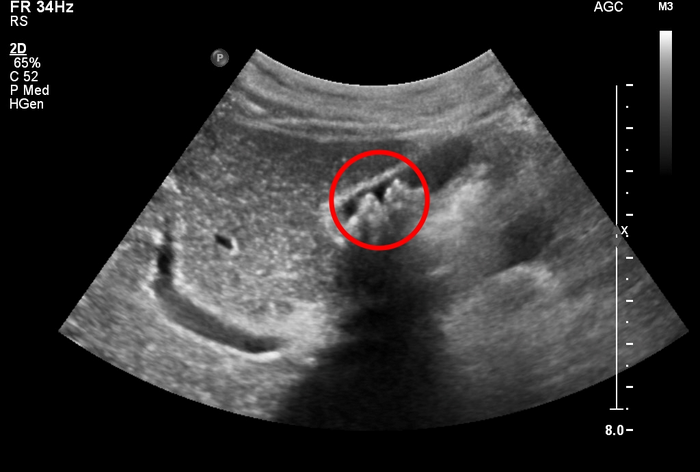

◇ 담낭에 생기는 돌 ‘담석’

담낭(쓸개)은 간 아래의 작은 주머니로 간에서 생성된 담즙을 저장하는 역할을 한다.

저장된 담즙은 음식물이 들어오면 담도(담관)를 통해 십이지장으로 분비되어 지방 음식 소화, 콜레스테롤 대사, 독성 물질 배출 등의 기능을 한다.

담즙에는 콜레스테롤, 담즙엽, 빌리루빈이라는 물질이 적절하게 균형을 맞춰 포함되어 있다. 이러한 균형이 깨지면 담즙은 결정화가 되어 담낭 내에 돌처럼 딱딱하게 변하는 담석이 된다.